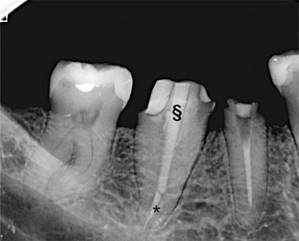

El CBCT (Vatech Pax Zenith CBCT machine, 120 kVp and 9.0 mA, FOV 8 × 6 cm, voxel size 0.12 mm) fue visualizado utilizando el software GALILEOS Viewer 1.9 (SICAT GmbH & Co. KG, Bonn, Germany), obteniendo una imagen tridimensional del diente para su evaluación en secciones axiales, sagitales y coronales. Las imágenes confirmaron la presencia de una sola raíz con un único canal de forma ovalada, extendido desde la cámara pulpar al ápice, correspondiendo al mencionado tipo I de Vertucci (Figura 2).

Figura 2: CBCT, múltiples imágenes en corte axial. Nótese la continuidad de un único canal sin presencia de canales accesorios (*)